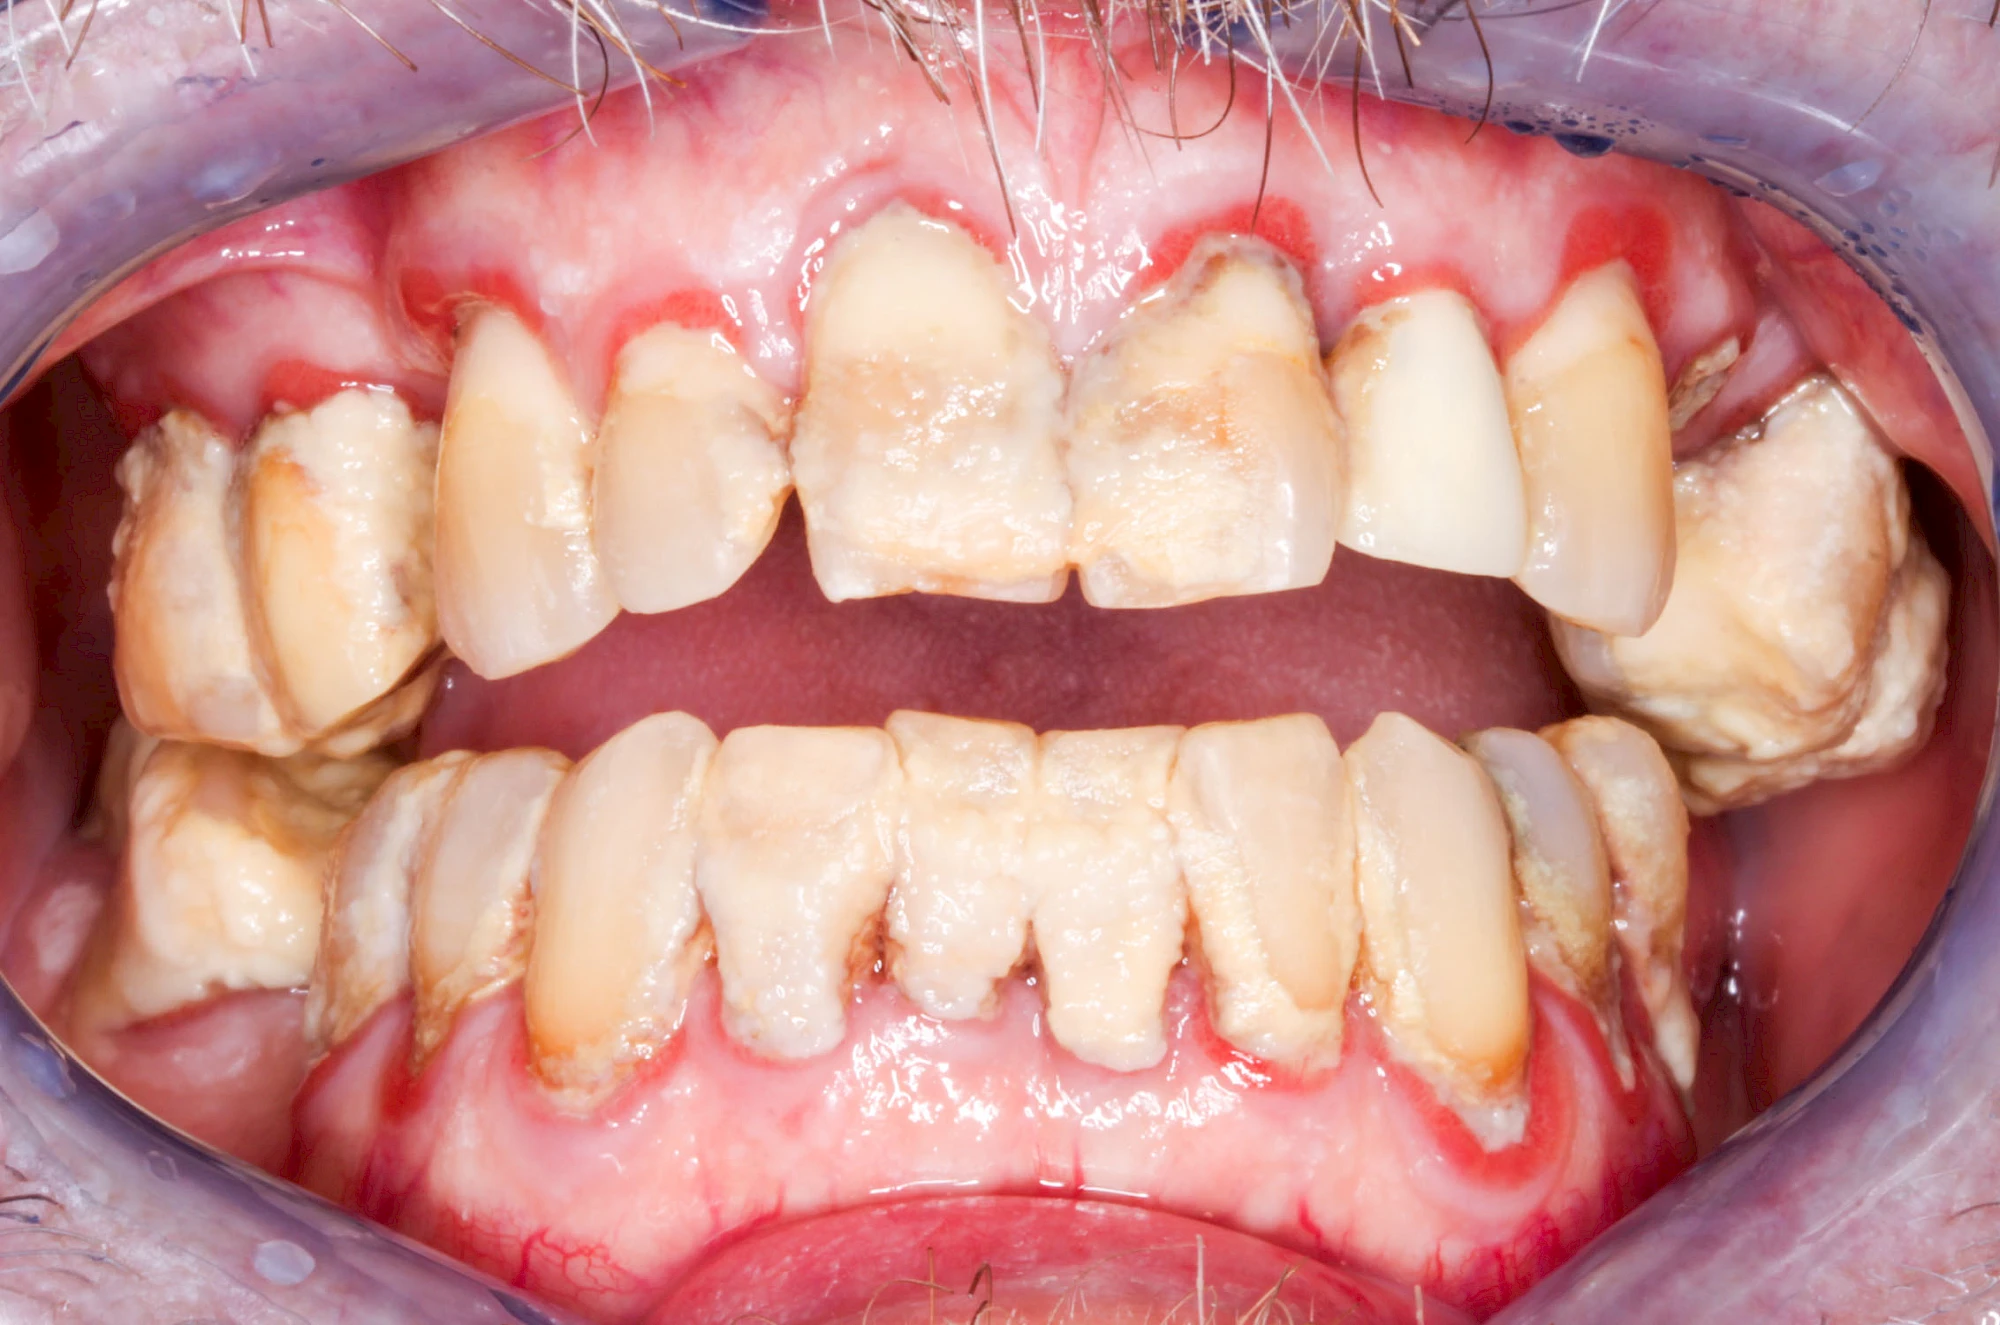

Bakterien in den Zahnbelägen greifen neben den Zähnen auch das Zahnfleisch (Gingiva) und den gesamten Zahnhalteapparat (Parodont) an. Der Körper reagiert mit einer Entzündung, sichtbar als Rötung und Schwellung. Meist blutet das Zahnfleisch z .B. beim Essen oder auch beim Putzen der Zähne.

Ist zunächst nur das Zahnfleisch von der Entzündung betroffen, spricht man von Gingivitis. Später, wenn auch der Knochen um die Zähne herum entzündet ist, spricht man von einer Parodontitis. Bei der Parodontitis wird der Knochen nach und nach abgebaut und das Zahnfleisch zieht sich zurück. Die Zahnhälse und Zahnwurzeloberflächen liegen mehr und mehr frei. Die Zähne werden zunehmend lockerer und fallen schließlich aus.